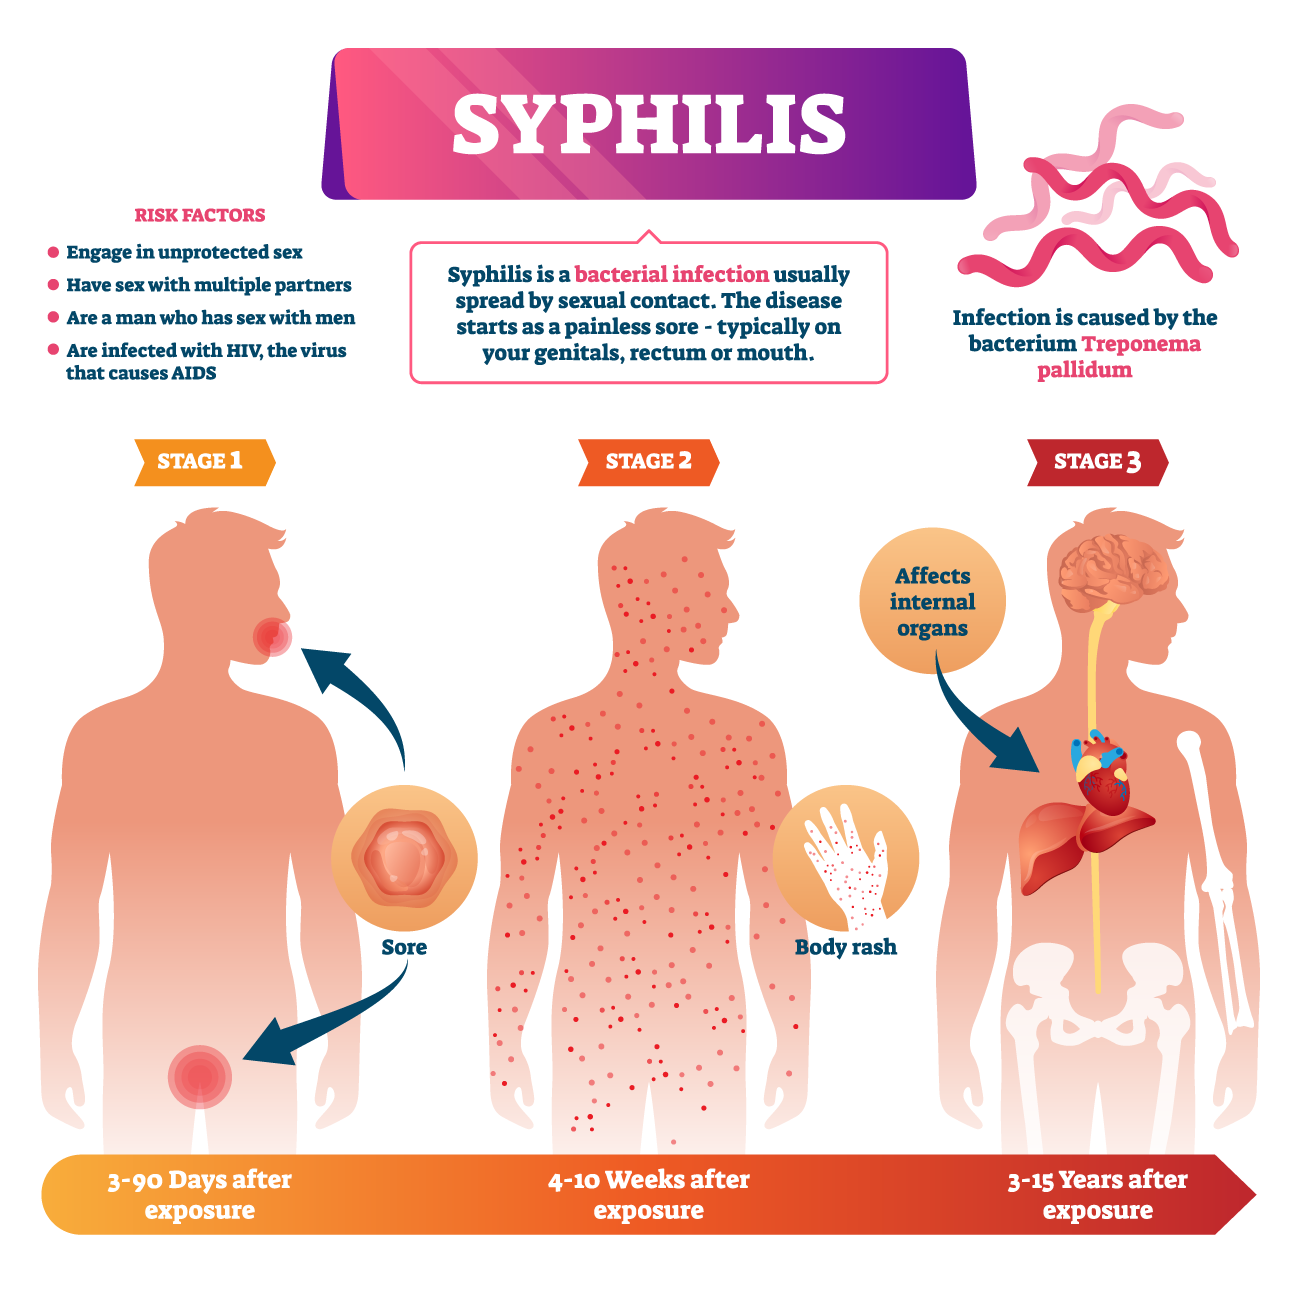

Stages of Syphilis: Symptoms, Causes, Prevention, and Treatment

Syphilis – Symptoms | Risk Factors | Treatments | Prevention

Syphilis

Syphilis: causes, symptoms, prevention and treatment

Signs and Symptoms – syphilis-the great imitator

Syphilis